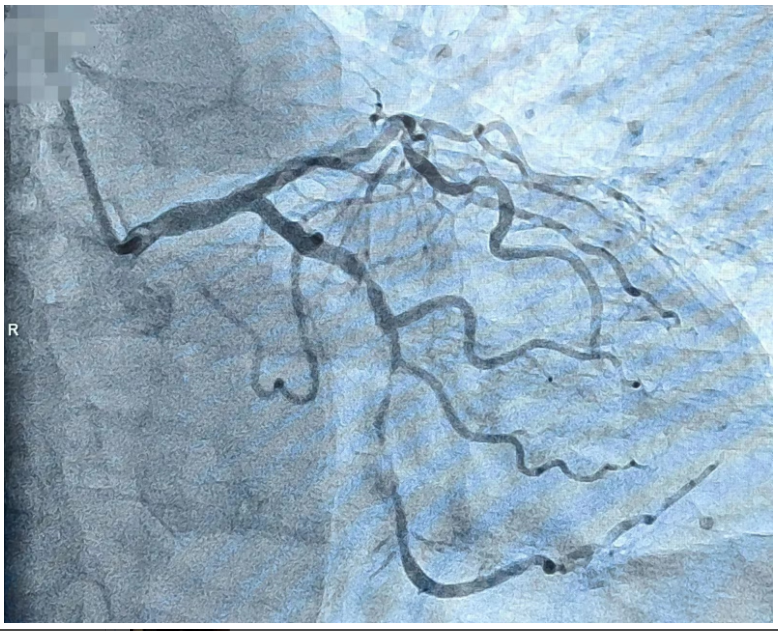

术中从桡动脉建立一条通路,先后完成了冠状动脉及椎动脉、颈动脉、脑动静脉造影,术中发现患者冠状动脉回旋支重度狭窄,前降支中度狭窄,双侧颈内动脉、左侧大脑中动脉轻-中的狭窄。综合患者情况及造影结果,冠状动脉有介入指征,脑血管无需介入处理,最终决定对患者冠状动脉重度狭窄行介入治疗,术中结合 IVUS(血管内超声),成功「重塑」患者冠状动脉,恢复心脏供血。(术者:杨征 助手:何涛志)